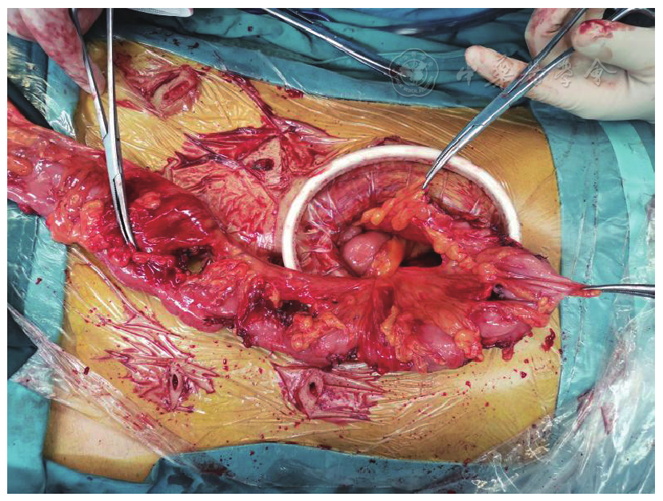

图3 离体标本。3A:切除肠管内部,可见较大隆起肿物及大量腺瘤样息肉,肿物大小与位置均与术前影像检查相符;3B:切除肠管外部

图7 造口还纳术中,回肠-回肠吻合